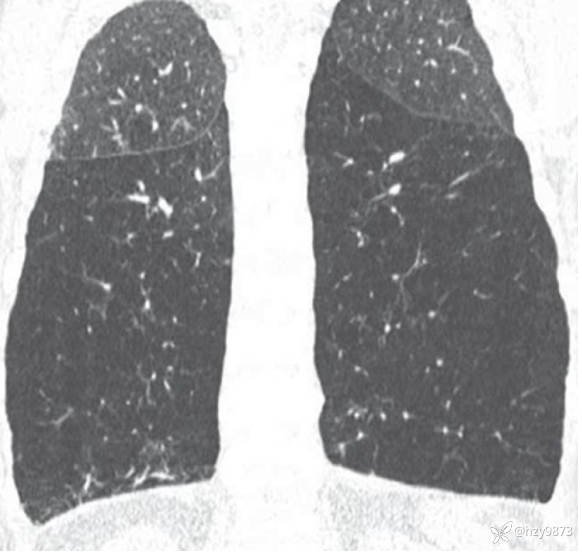

Fleischner 学会将肺气肿分为三类:

1) 小叶中央型肺气肿(centrilobular emphysema)

2) 全小叶型肺气肿(panlobular emphysema)

3) 间隔旁气肿(paraseptal emphysema)